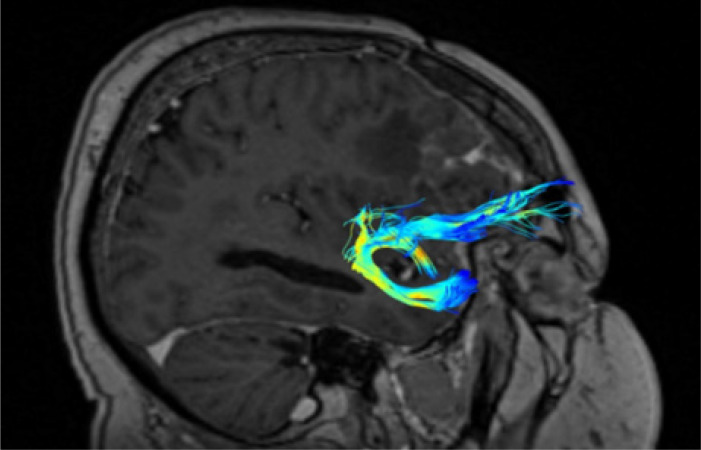

Diffusion tensor imaging (DTI) and tractography are powerful non-invasive techniques for studying the human brain's white matter pathways. The uncinate fasciculus (UF) is a key frontotemporal tract involved in emotion regulation, memory, and language. Despite advancements, challenges persist in accurately mapping its structure and function due to methodological limitations in data acquisition and analysis. This review aims to provide a comprehensive overview of the strengths and limitations of DTI and tractography in studying the UF, focusing on its anatomy, data acquisition techniques, and associated neurological and psychiatric disorders. A systematic review of over 30 years of literature on UF was conducted, encompassing anatomical studies, DTI methodologies, and clinical applications. Studies involving both postmortem dissections and in vivo imaging were analysed, with particular attention to different DTI acquisition parameters, fibre tracking algorithms, and their impact on imaging accuracy. DTI has significantly improved our understanding of UF anatomy and its role in neurocognitive functions. However, methodological constraints such as low spatial resolution, crossing fibres, and inter-subject variability limit its precision. Advances in higher-field magnetic resonance imaging, improved diffusion models, and artificial intelligence-enhanced tractography offer promising solutions. UF abnormalities have been linked to various disorders, including schizophrenia, depression, autism spectrum disorders, and neurodegenerative diseases. While DTI and tractography are invaluable tools for studying the UF, their limitations necessitate cautious interpretation of results. Future research should focus on refining imaging techniques to enhance accuracy and clinical applicability, paving the way for better diagnostic and therapeutic strategies.